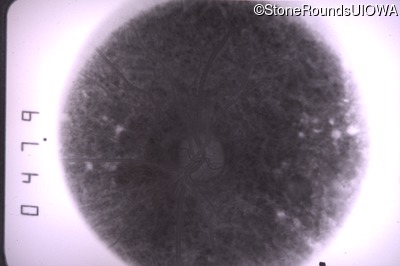

Goldmann Visual Field - Right - 20/20 sc

Exemplar